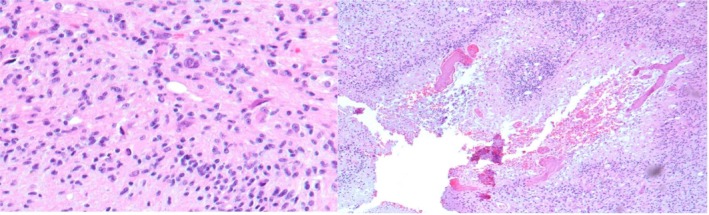

This study aimed to evaluate the performance of ChatGPT-4.0 as a diagnostic support tool for pathologists in identifying different types of gliomas based on histopathological data and to compare its performance with that of another artificial intelligence tool (Gemini 2.5 Pro). A retrospective analysis was performed on 25 cases with histopathological descriptions. The dataset, anonymized for patient confidentiality, included clinical details such as age, sex, and site, along with two histological images for each case, obtained from the archive files of the Anatomic Pathology section, Department of Medical, Surgical Sciences and Advanced Technologies "G.F. Ingrassia" University of Catania, Italy. ChatGPT-4.0 was tasked with generating diagnoses, which were classified as correct, similar, or different when compared to the pathologists' conclusions and the diagnoses provided by Gemini. ChatGPT-4.0 achieved a diagnostic accuracy of 88%, correctly identifying 22 out of 25 cases. No significant differences in diagnostic performance were observed between male and female patients. The AI performed exceptionally well in diagnosing glioblastomas, with a 100% accuracy rate, while two oligodendrogliomas and one astrocytoma IDH-mutant G3 were misdiagnosed. A comparative evaluation with Gemini 2.5 Pro was also conducted, although its contribution was limited to a qualitative comparison based on the same dataset. ChatGPT-4.0 demonstrated moderate accuracy in the histopathological diagnosis of gliomas, with little variability depending on glioma subtype. While its performance highlights potential for future integration into clinical workflows, significant improvements are required to ensure its reliability and effectiveness in diagnostic applications. Trial Registration: ce 165/2015/PO.

Abstract Image